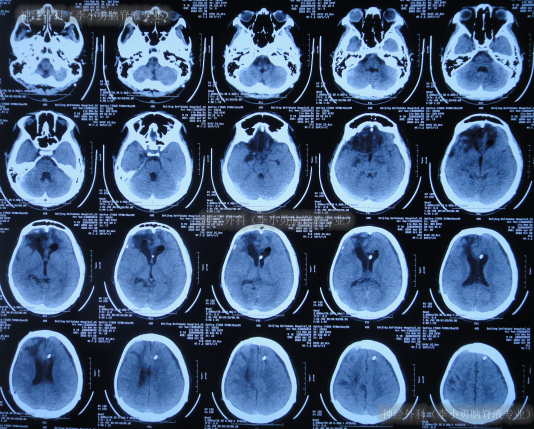

患者于2022年2月2日,不慎摔倒头部磕到地面,当时呈嗜睡状态,呕吐1次,大小便失禁,由120急送至当地县某医院,查头颅CT示右额部血肿(片子丢失),当即转至上级的河北省唐山市某医院,查头颅CT示右额部血肿、脑疝(图-1);检查期间出现昏迷、呕吐、四肢强直。

图-1:2022年2月2日头颅CT

急诊当天进行了去骨瓣减压+血肿清除术(图-2)。

图-2:2022年2月2日术后头颅CT

去骨瓣减压+血肿清除术后第2天即2022年2月3日,头颅CT示出血有增多(图-3)。

图-3:2022年2月3日头颅CT

术后3天即2022年2月4日,患者苏醒,能言语,但遗留左侧肢体不能活动,低钠血症,查头颅CT示仍有较多积血(图-4)。

图-4:2022年2月4日头颅CT

继续治疗1月期间出现数次呕吐,行胃肠镜检查未见异常(片子丢失),给予胃管及肠管置管,期间5次查头颅CT(图-5)均示脑室逐渐出现扩张,并加重。

图-5:5次查头颅CT

去骨瓣减压术后36天即2022年3月9日,复查头颅CT(图-6)示脑室扩张更严重了,脑膨出。

图-6:2022年3月9日头颅CT

去骨瓣减压术后43天即2022年3月16日,查头颅CT示仍严重脑积水(图-7)。

图-7:2022年3月16日头颅CT

因脑积水进一步加重,于2022年3月28日(去骨瓣减压术后55天),进行了脑室腹腔分流术。术后次日查头颅CT示脑室分流术后有出血(图-8)。

图-8:2022年3月29日头颅CT

脑室腹腔分流术后4天即2022年4月1日,查头颅CT示脑室明显缩小(图-9)。

图-9:2022年4月1日头颅CT

脑室腹腔分流术后8天即2022年4月5日,查头颅CT示脑室周仍有水肿(图-10)。

图-10:2022年4月5日头颅CT

脑室腹腔分流术后31天即2022年4月28日,查头颅CT示脑室又变大(图-11)。

图-11:2022年4月28日头颅CT